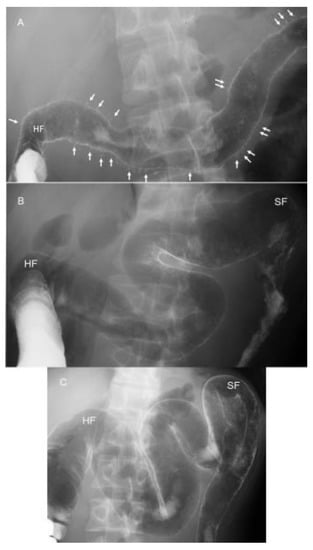

- Chiba, M.; Tsuji, T.; Nakane, K.; Tsuda, S.; Ishii, H.; Ohno, H.; Obara, Y.; Komatsu, M.; Sugawara, T. High remission rate with infliximab and plant-based diet as first-line (IPF) therapy for severe ulcerative colitis: Single-group trial. Perm. J. 2020, 24, 1–10. [Google Scholar] [CrossRef] [PubMed]

- Altaras, J. Radiologic features of inflammatory diseases of the colon. In Radiologic Atlas of the Colon and Rectum; Altaras, J., Ed.; Urban & Schwarzenberg Inc.: Baltimore, MD, USA, 1984; pp. 101–180. [Google Scholar]